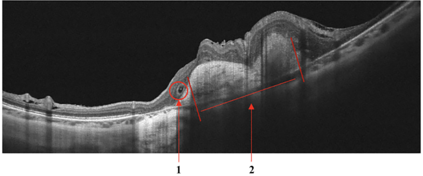

Optical coherence tomography (OCT) is a non-invasive imaging technique with extensive clinical applications in ophthalmology. OCT enables the visualization of the retinal layers, playing a vital role in the early detection and monitoring of retinal diseases. OCT uses the principle of light wave interference to create detailed images of the retinal microstructures, making it a valuable tool for diagnosing ocular conditions. This work presents an open-access OCT dataset (OCTDL) comprising over 1600 high-resolution OCT images labeled according to disease group and retinal pathology. The dataset consists of OCT records of patients with Age-related Macular Degeneration (AMD), Diabetic Macular Edema (DME), Epiretinal Membrane (ERM), Retinal Artery Occlusion (RAO), Retinal Vein Occlusion (RVO), and Vitreomacular Interface Disease (VID). The images were acquired with an Optovue Avanti RTVue XR using raster scanning protocols with dynamic scan length and image resolution. Each retinal b-scan was acquired by centering on the fovea and interpreted and cataloged by an experienced retinal specialist. In this work, we applied Deep Learning classification techniques to this new open-access dataset.